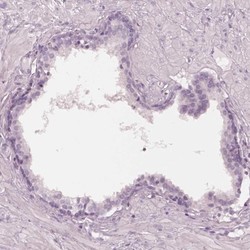

- Submitted by

- Novus Biologicals (provider)

- Main image

- Experimental details

- Immunohistochemistry-Paraffin: FAM154B Antibody [NBP1-90521] - Staining of human prostate shows low expression as expected.